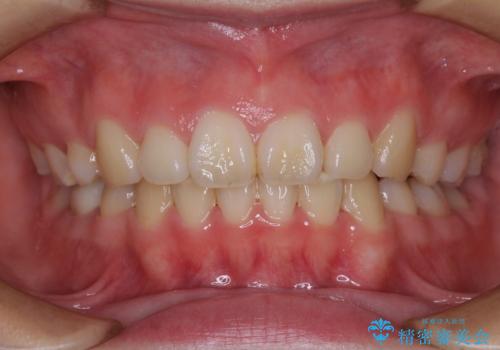

- 前歯のデコボコを気にして来院された患者様です。

叢生と捻転が随所に認められるものの、マウスピースで十分対応可能であったため、インビザラインにて矯正治療を行うこととしました。